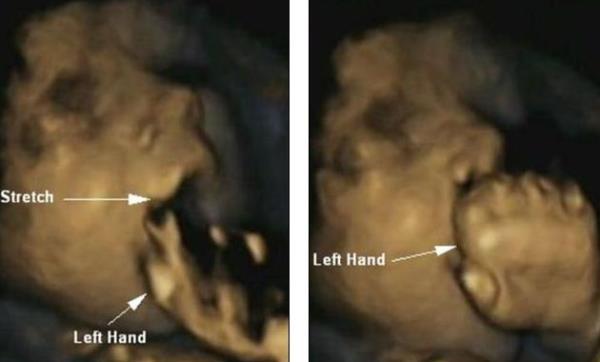

توصل باحثون، للمرة الأولى، عبر مجموعة صور ثلاثية الأبعاد، إلى أن الأجنة في بطون أمهاتهم يتعلمون طريقة توقع اللمس، وذلك في الوقت الذي تبين فيه أن طريقة لمسهم لوجوههم ورؤوسهم قد تكون مؤشراً لمدى نموهم نفسياً وبدنياً قبل أن يولدوا.

اكتشف علماء نفس أن الأجنة يكونون قادرين على التنبؤ، بدلاً من الاستجابة، بحركات أيديهم تجاه أفواههم، مع دخولهم المراحل الأخيرة من الحمل مقارنةً بالمرحلة الأولى. وأوضح الباحثون في هذا السياق أن اكتشافهم هذا قد يحسن فهمهم بخصوص الأطفال الرضع، خاصة الذين يولدون قبل الأوان المحدد لهم، واستعدادهم للتفاعل إجتماعياً وقدرتهم على تهدئة أنفسهم عن طريق مص إصبع الإبهام أو مص الأصابع كلها.

وجاء هذا الكشف بعدما وجدت دراسة سابقة أن الأجنة يتبرزون في الرحم، ربما كممارسة قبل أن يولدوا. واستعانت دكتور ريسلاند وبصحبتها فريق من الباحثين بقيادة جامعة دورهام بصور فحوصات مأخوذة بالأشعة فوق الصوتية "رباعية الأبعاد" لتصوير 8 فتيات و7 صبية مرة كل شهر بين أسابيع الحمل رقم 24 و36.

وأظهر الصبية والبنات نفس معدل النمو أثناء الدراسة البحثية. ولاحظ الباحثون أن الأجنة كانوا يلمسون الجزء العلوي وجوانب رؤوسهم في المرحلة الأولى من الحمل، وأنهم بدأوا يلمسون الجزء السفلي، والأكثر حساسية، من وجوههم وأفواههم.